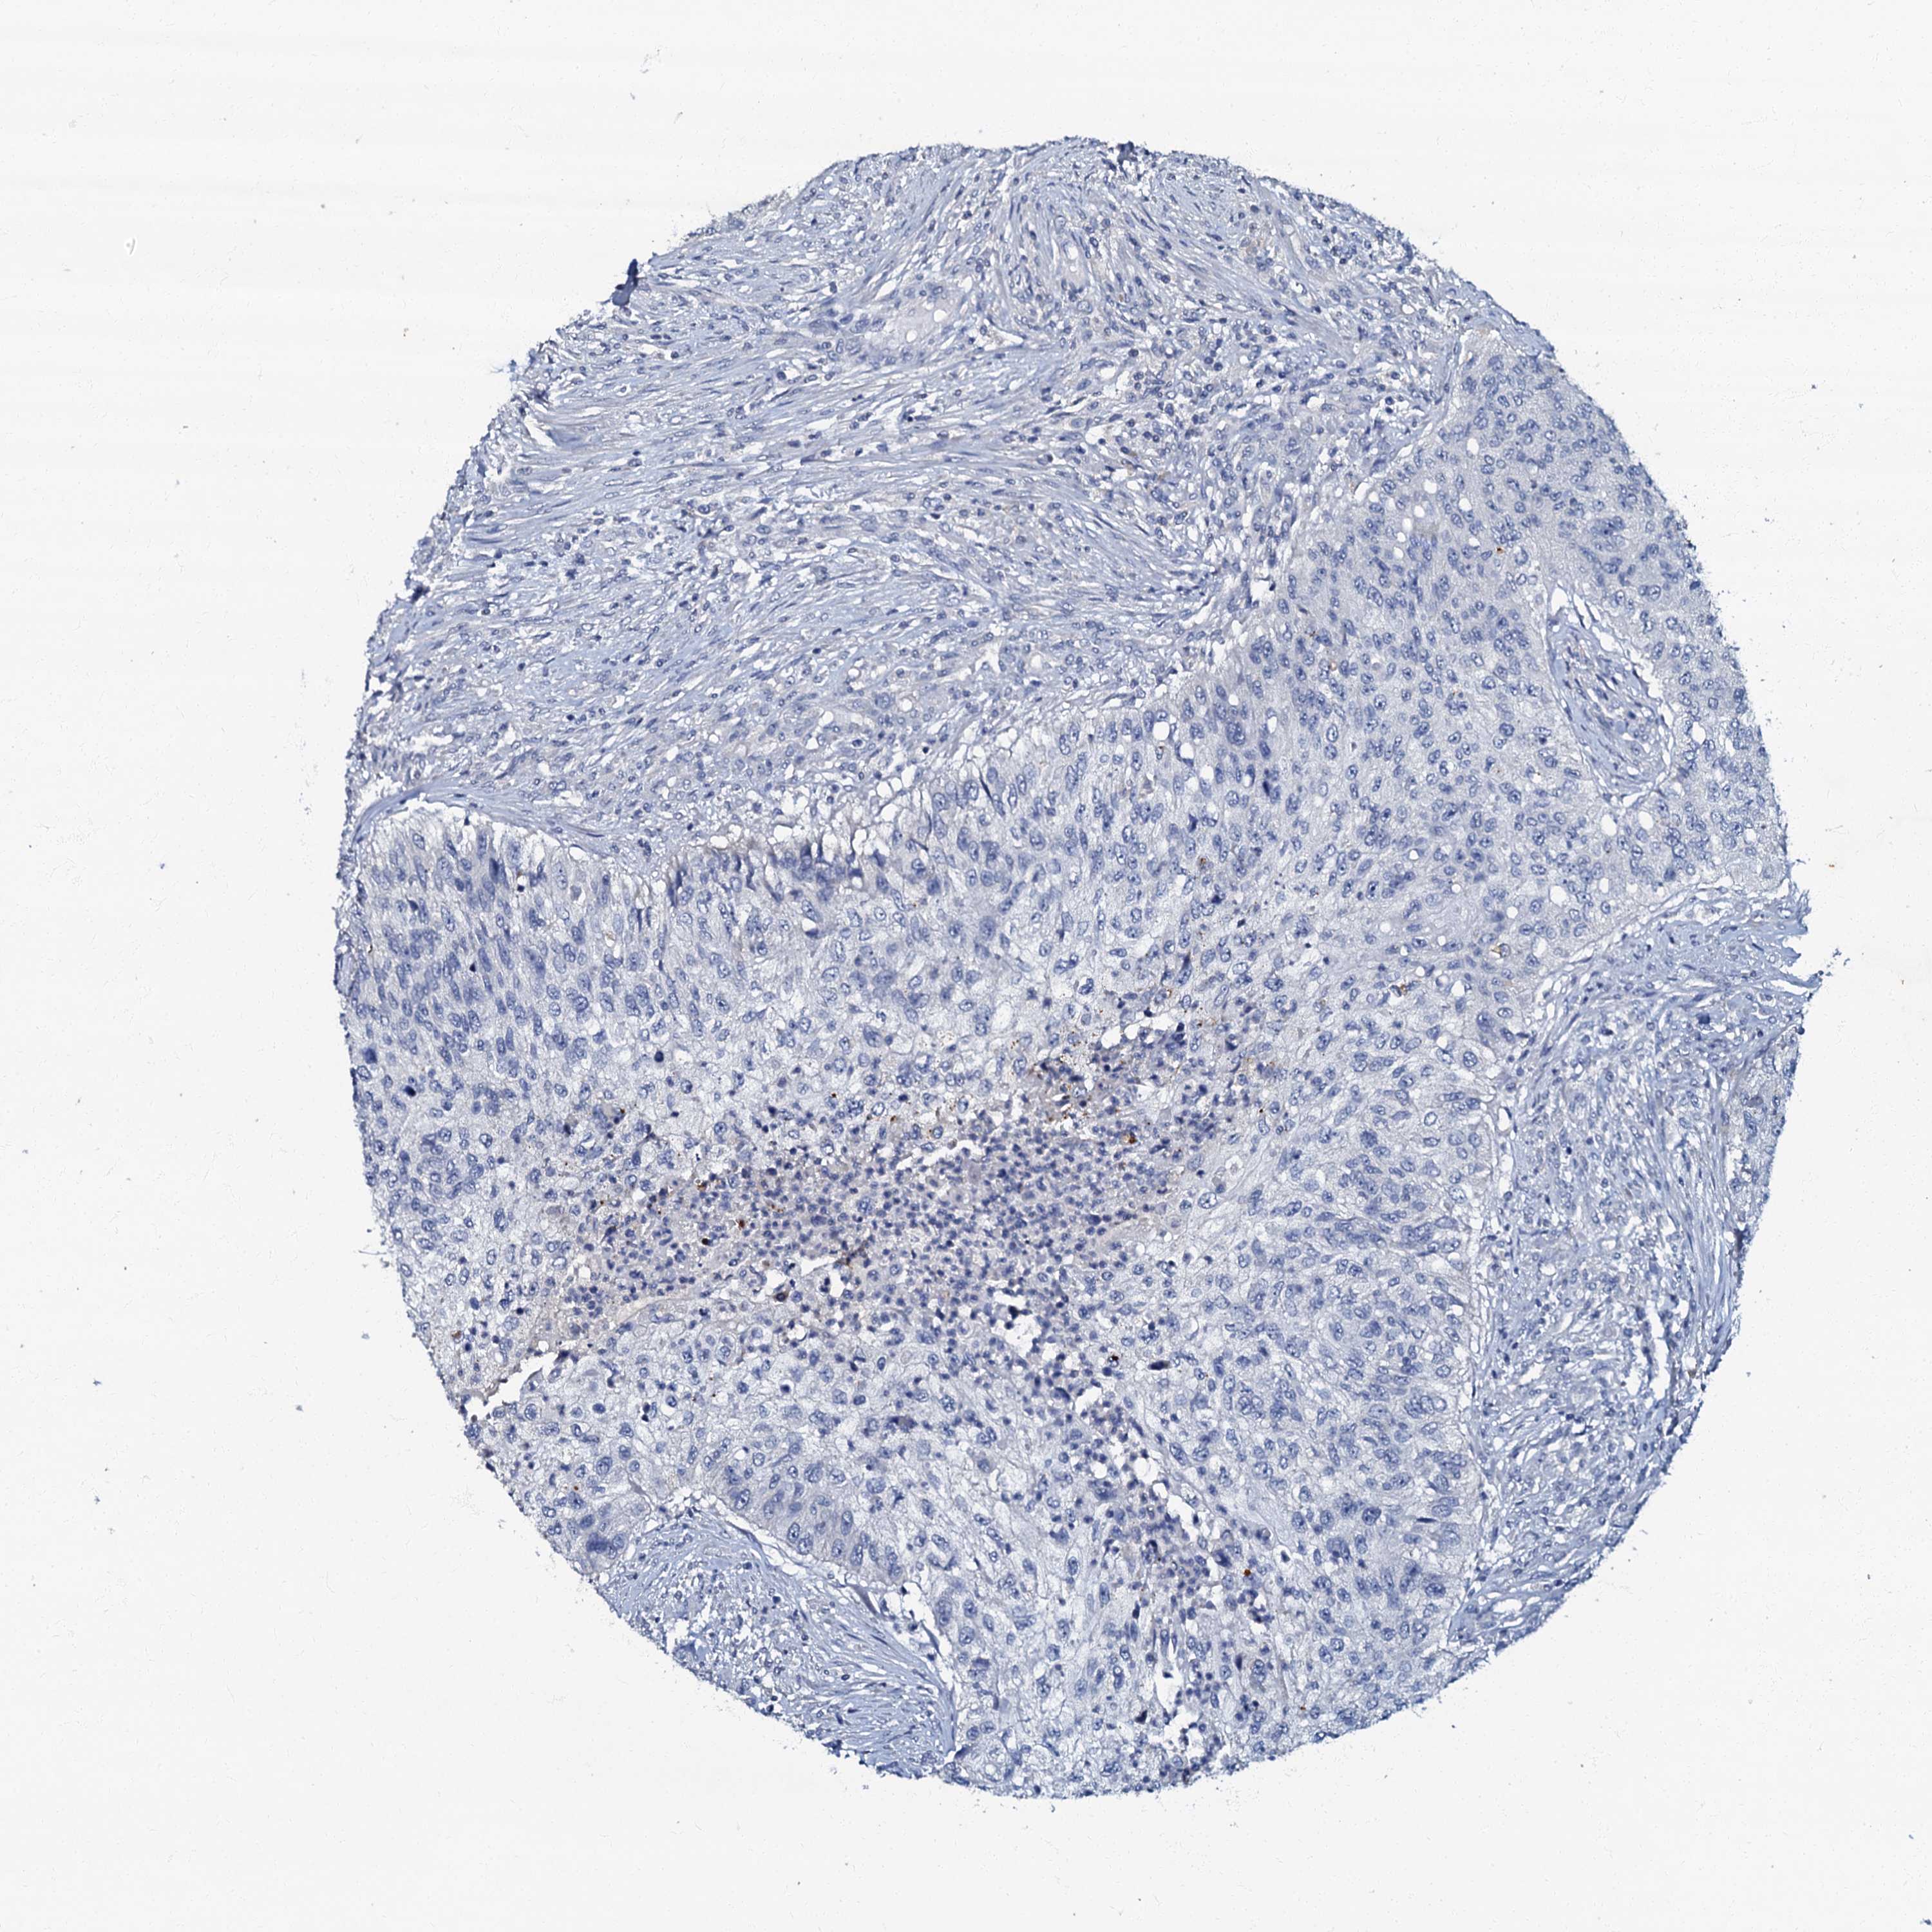

UROTHELIAL CANCER - Protein expressioni

A mouse-over function shows sample information and annotation data. Click on an image to view it in a full screen mode. Samples can be filtered based on level of antibody staining by selecting one or several of the following categories: high, medium, low and not detected. The assay and annotation is described here.

Antibody stainingi

Antibody staining in the annotated cell types in the current human tissue is reported as not detected, low, medium, or high, based on conventional immunohistochemistry profiling in selected tissues. This score is based on the combination of the staining intensity and fraction of stained cells.

Each image is clickable and will lead to virtual microscopy that enables deeper exploration of all samples and also displays staining intensity scores, fraction scores and subcellular localization as well as patient and tissue information for each sample.

Antibody HPA037947

Antibody HPA037948

Staining

High

Medium

Low

Not detected

Intensity

Strong

Moderate

Weak

Negative

Quantity

>75%

75%-25%

<25%

None

Location

Nuclear

Cytoplasmic/membranous

Cytoplasmic/membranous,nuclear

Urothelial carcinoma, High grade

Urothelial carcinoma, Low grade

Urothelial carcinoma, NOS